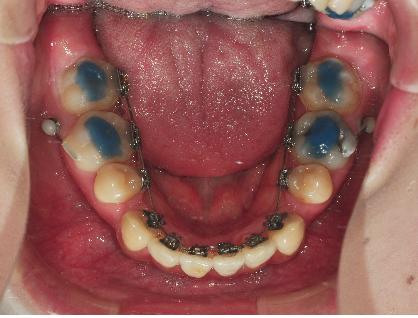

이번 월치료에는 와이어교체와 훅부착하였습니다.

와이어를 약간 더 굵은 걸로 교체하였는데요 ,

와이어가 굵어서 그런지 브라켓이 잘 안 닫겨 선생님들께서 고생하셨는데요ㅠㅠ

닫기기는 하나 와이어의 굵기에 못 이겨 다시 열릴까바 염려하셔서

열릴 꺼 같은 브라켓에는 철사로 묶어주셨어요ㅠㅠ

와이어를 연결하면서 하나 더 새로운 장치를 부착했어요~

바로 ‘훅’이라는 장치인데요, 이 장치의 역할은 저의 치아치료에서는

앞니쪽부분을 들어올리는 역할을 하게 될 거라구 하셨어요~

그래서 ‘훅’을 이용해 앞니를 올리는 치료를 하였습니다.